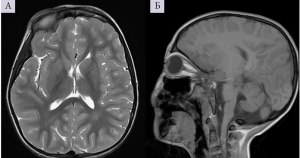

Клинических рекомендаций по диагностике и лечению СМ в настоящее время не разработано. На сегодняшний день лабораторные маркеры этой патологии неизвестны, поэтому диагностика СМ основывается на анализе клинической картины и характера прогрессирования заболевания. Применяемые нейровизуализационные методы (компьютерная томография, магнитно-резонансная томография, магнитно-резонансная трактография) лишь подтверждают диагноз. Выявляется асимметричный локальный атрофический процесс, который затрагивает моторную кору и/или пирамидный путь (рис.1, 2, 3).